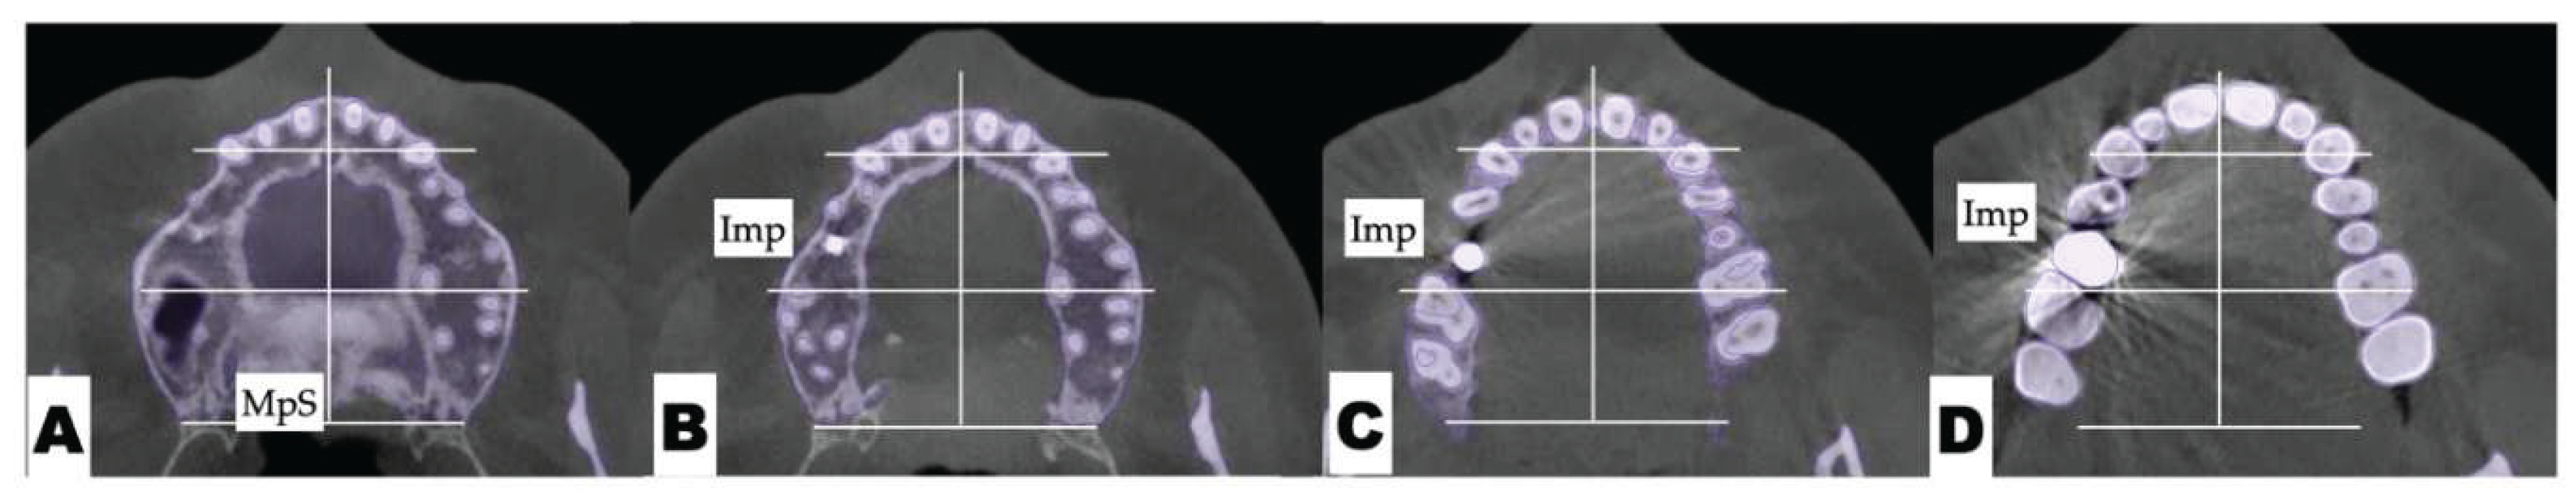

Background: While mini-screw-assisted rapid palatal expansion (MARPE) is effective for correcting maxillary transverse deficiency in adults, perimaxillary suture disarticulation—particularly at the pterygomaxillary junction—can be inconsistent. This study evaluates skeletal and dentoalveolar outcomes of a novel 3D-guided midpalatal piezocorticotomy-assisted MARPE protocol, focusing on expansion symmetry and pre-existing asymmetries. Methods: Three adult patients were retrospectively analyzed after treatment with 3D-guided midpalatal piezocorticotomy-assisted MARPE expansion and one with non-guided midpapalatal piezocorticotomy and MARPE expansion. Surgical guides were digitally designed using CBCT data to align with the nasal septum orientation in multiple planes. Perimaxillary suture disarticulation was measured pre- and post-expansion, and dentoalveolar changes were evaluated. Post-expansion asymmetries were addressed using directly printed aligners. Results: Complete midpalatal suture separation (mean 8.48 mm), involving both anterior and posterior nasal spine regions, was achieved in one patient. Bilateral pterygomaxillary disarticulation averaged 1.06–1.23 mm, resulting in forward–outward rotation of the nasomaxillary complex. Additional separation occurred at the frontonasal (2.03 mm) and vomeromaxillary (1–2 mm) sutures, with no significant changes in orbital or peri-orbital sutures. One patient presented with pre-existing dentoalveolar asymmetry, which intensified the perceived post-expansion imbalance but was successfully corrected with directly printed aligners. In the second case, 5.6 mm of suture separation resulted in a limited lateral nasal width increase (<1.5 mm), while maxillary base expansion exceeded 6 mm. A significant canine plane cant (1.2 mm) and divergent axial inclinations of the maxillary central incisors relative to the palatal plane were also observed. In the second case, a non-impactful palatal bone fracture with asymmetric displacement of the left palatine fragment was documented. After 16 months of aligner therapy, all cases exhibited favorable remodeling of the palatal structures, midpalatal suture, and alveolar processes, accompanied by improved dental alignment, occlusal plane symmetry, and mandibular dentoalveolar adaptation. The dento-alveolar expansion achieved in the third case over the course of 16 months of treatment was approximated at 4 mm. The fourth case showed consistent improvement with direct printed aligners after MARPE midpalatal diasrticulation of 11 mm after experiencing minor bone fracture. Conclusions: Human skulls exhibit considerable variability between the left and right sides, which can influence spatial balance. Pre-existing cranial asymmetries appear to be the primary contributors to asymmetry following MARPE treatment. Careful evaluation of dentoalveolar discrepancies and axial tooth inclinations is essential for preventing and managing potential asymmetric dental arch outcomes during the post-expansion phase. Although peri-maxillary bone fractures are relatively uncommon, their occurrence is influenced by multiple factors. Adjunctive techniques, such as 3D-guided midpalatal piezocorticotomy, show promise in significantly lowering the risk of intra-expansion peri-maxillary fractures.